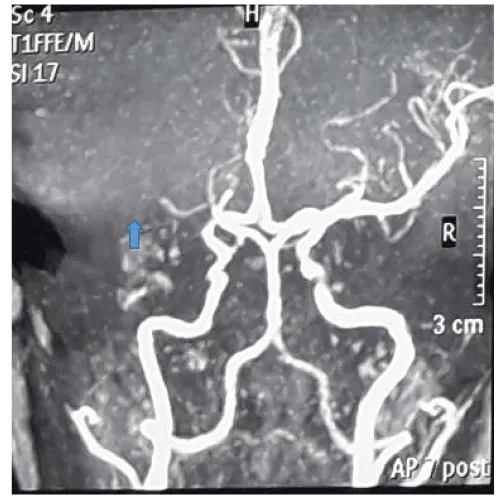

Magnetic resonance angiography showed left middle cerebral artery territory infarct involving the left ganglio-capsular region, left corona radiata and left frontotemporal lobe, suggestive of occlusion in the left middle cerebral artery (Figure 2).